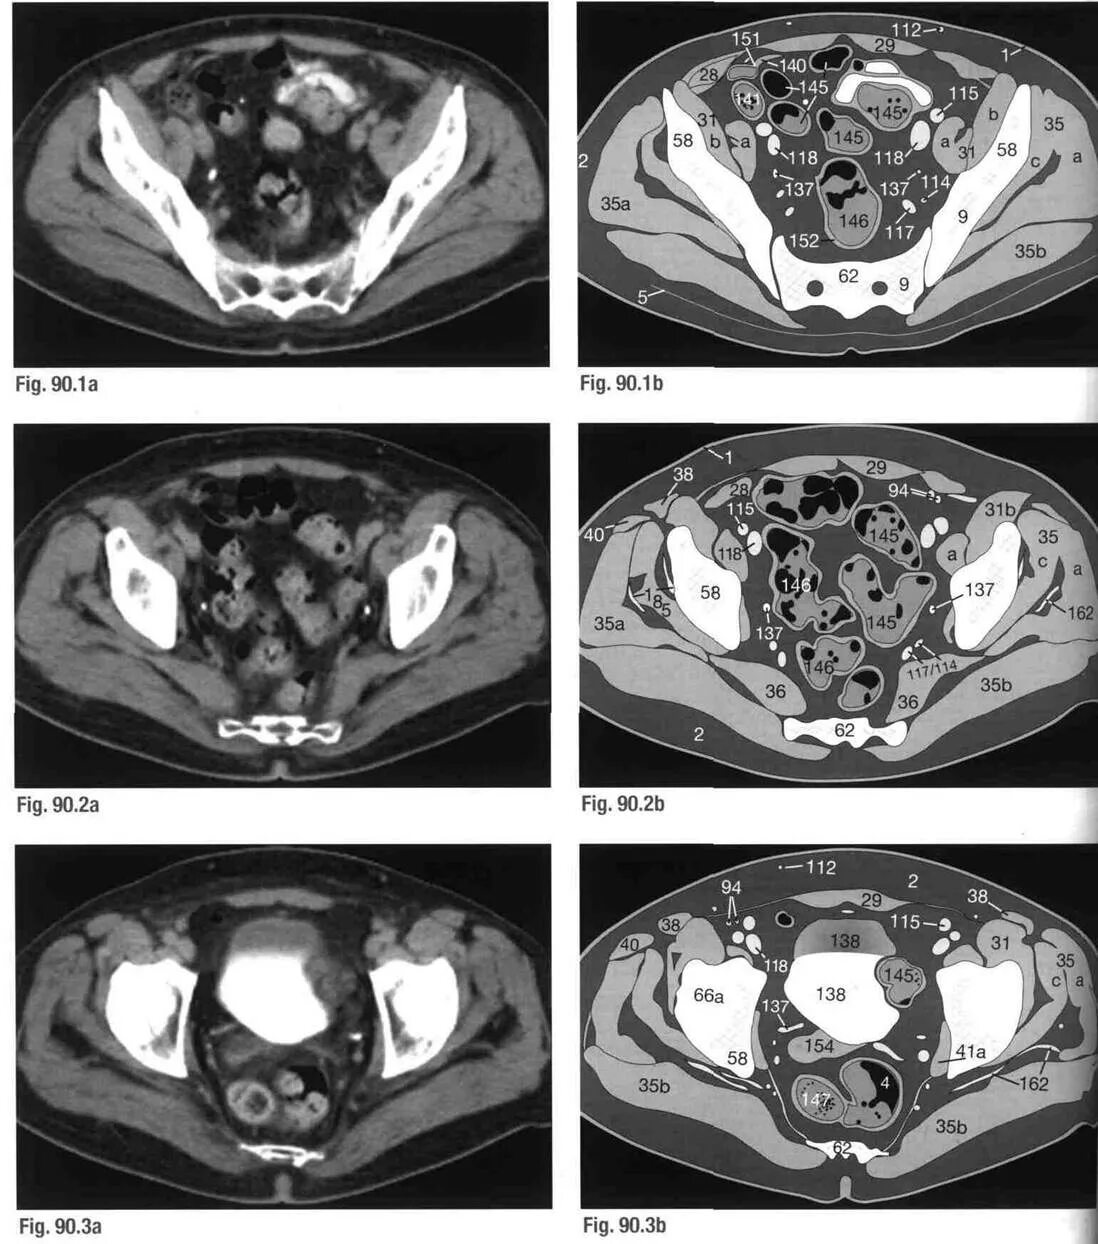

Кт делают с контрастом или нет